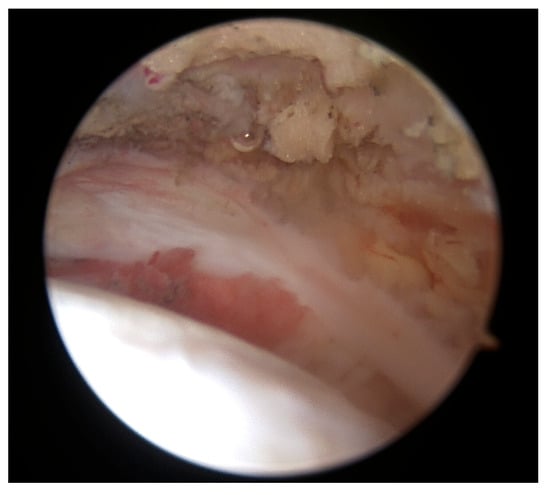

Once the intra-articular procedures were completed, the arthroscope was repositioned into the posterior subacromial space view. A GraftNet device (Arthrex, Munich, Germany) was used to harvest subacromial bursal tissue, serving both as an augmentation material and to improve visualization and measurements of the tear (Figure 2).

Figure 2.

Harvesting subacromial bursal tissue.